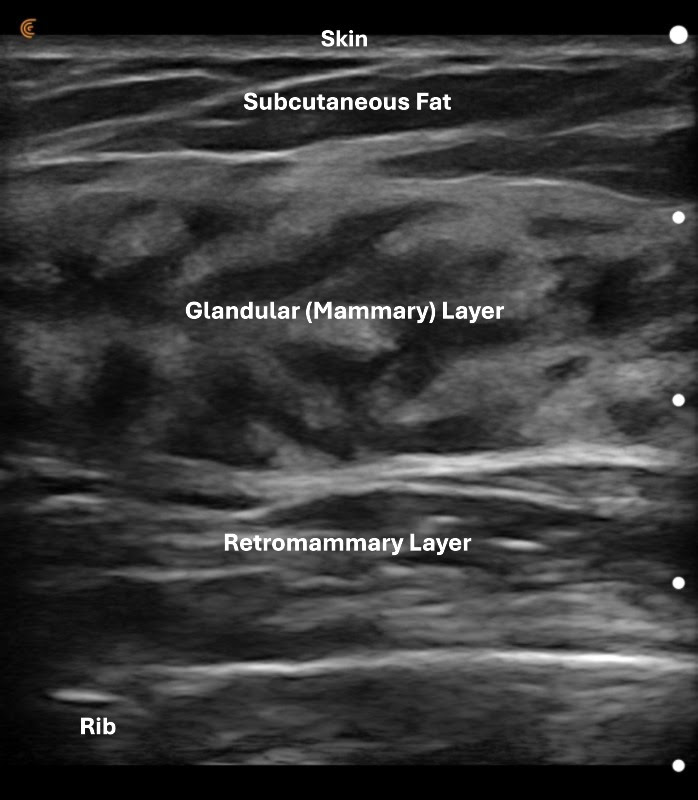

In the ultrasound image of a dense breast, you can clearly see that the glandular tissue layer is larger than the fatty layer. The image also shows that the ultrasound probe (called a transducer) can see all the way down to the ribs, which confirms that every layer of the breast has been examined. Seeing the breast from the skin all the way to the chest wall is very important for a thorough evaluation.

Women are diagnosed with dense fibrous breast tissue based on the balance between two main types of tissue in the breast. One type is glandular tissue, which is the working part of the breast, and the other is the fatty layer that sits just under the skin.

When a woman has more glandular tissue than fatty tissue, her breasts are considered dense. Density can vary—some women have moderately dense breasts, while others have extremely dense breasts.